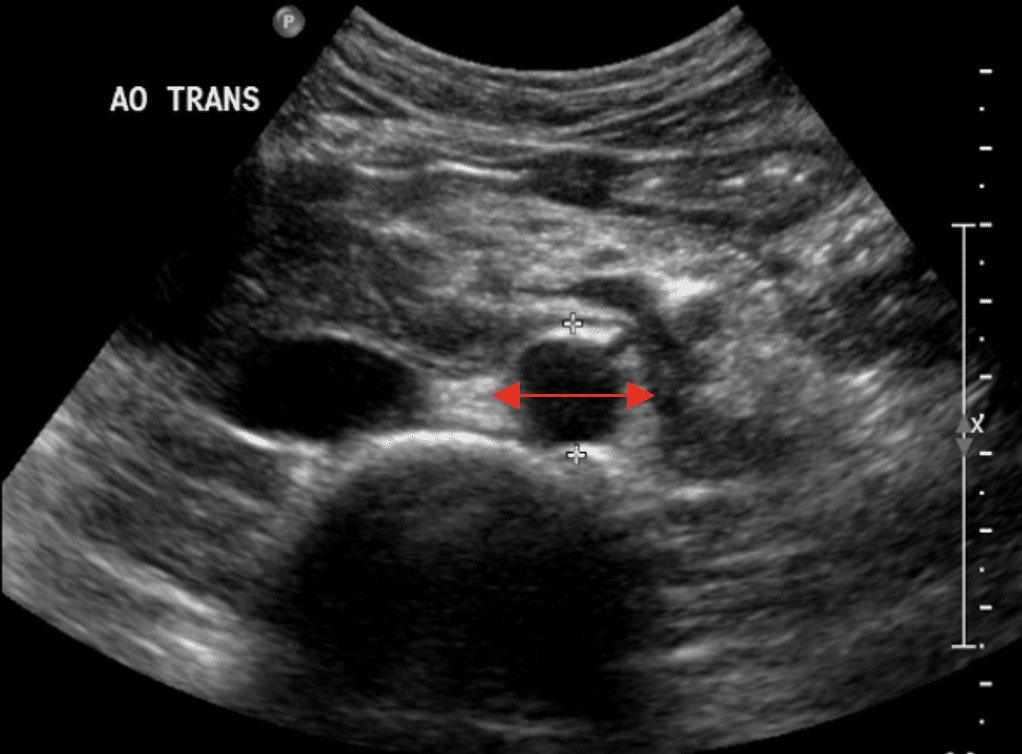

🧭 Technique

Utiliser la sonde convexe 2–5 MHz, patient en décubitus dorsal.

L’aorte est visualisée en longitudinal et transverse, depuis le diaphragme jusqu’à la bifurcation iliaque.

Le diamètre externe-externe doit être mesuré perpendiculairement au faisceau, sans compression.

- Diamètre normal : < 3 cm.

- Lumen anéchogène avec paroi fine et régulière.